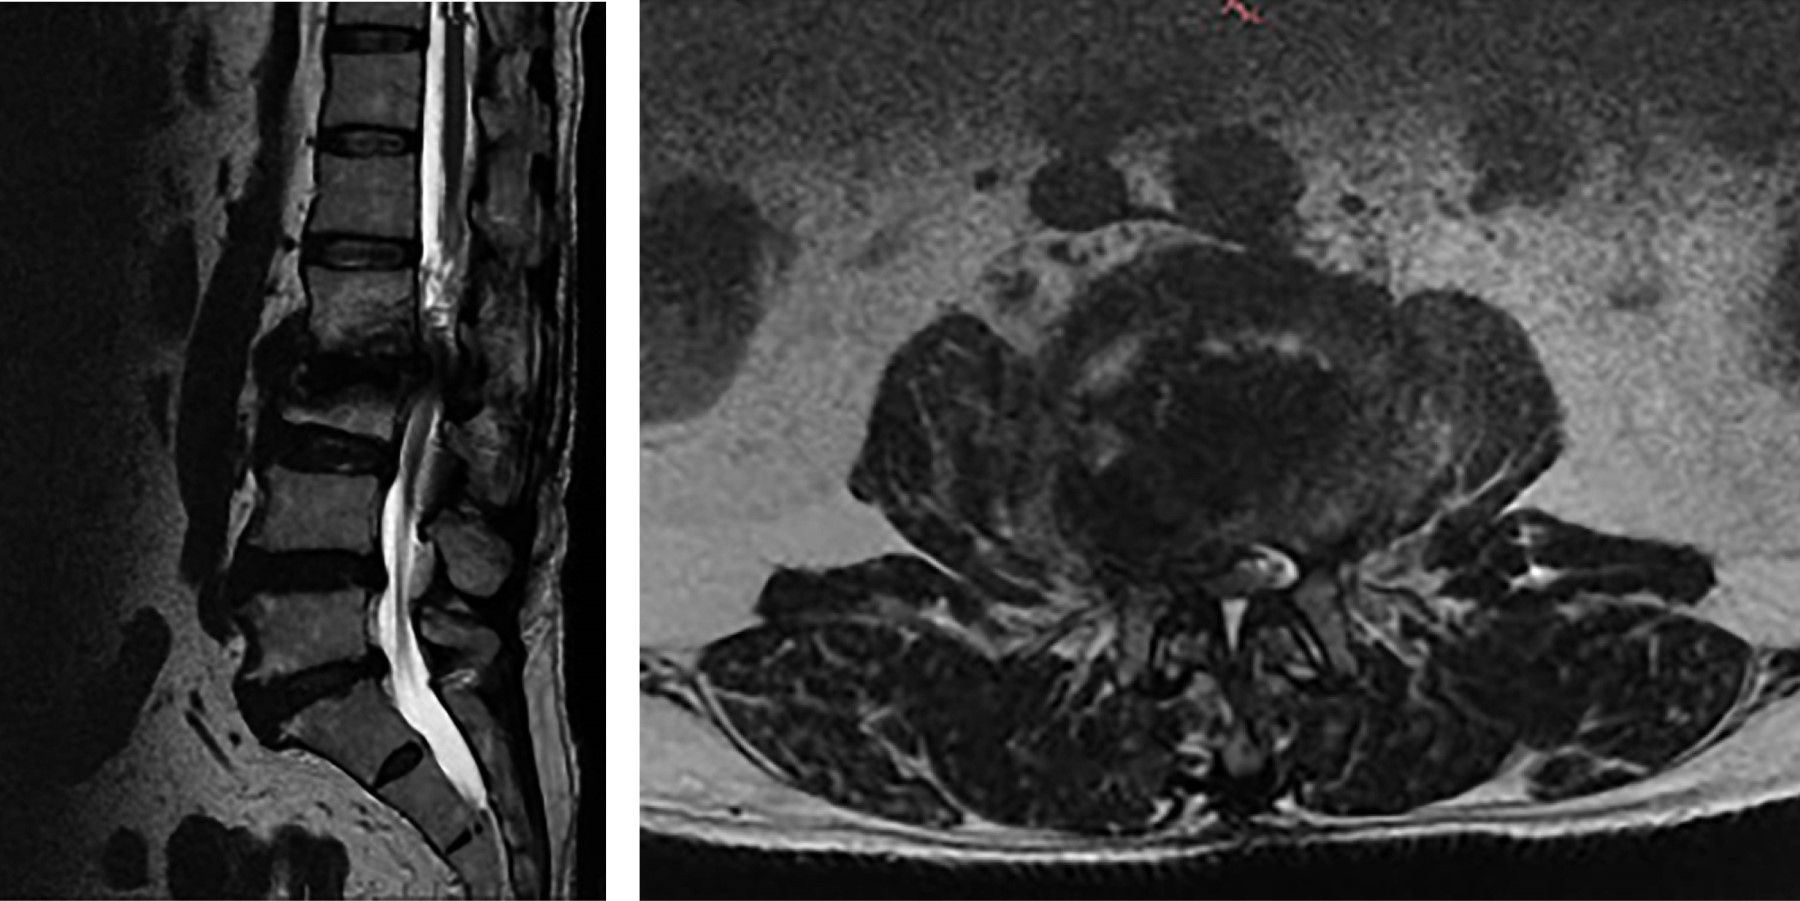

Se obtuvo un total de 51 pacientes diagnosticados con síndrome de destrucción vertebral (Figura 1 y 2). Se observó una incidencia mayor para el género masculino (n = 34) y que para el femenino (n = 17). La edad promedio fue 64.66 años (rango 25 a 85 años). Los cuerpos vertebrales afectados con mayor frecuencia fueron L4 con 18 casos, L2 con siete, L5 con siete y L3 con 11. En nuestra población, la primera causa del síndrome de destrucción vertebral fue de origen neoplásico con 34 casos confirmados mediante reporte histopatológico, seguido por los de origen infeccioso con nueve casos y, por último, los de origen metabólico con ocho casos.